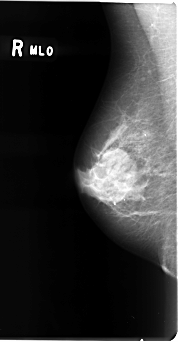

B_3076_1.RIGHT_MLO

RIGHT_MLO LINES 4784 PIXELS_PER_LINE 2488 BITS_PER_PIXEL 12 RESOLUTION 50 NON_OVERLAY